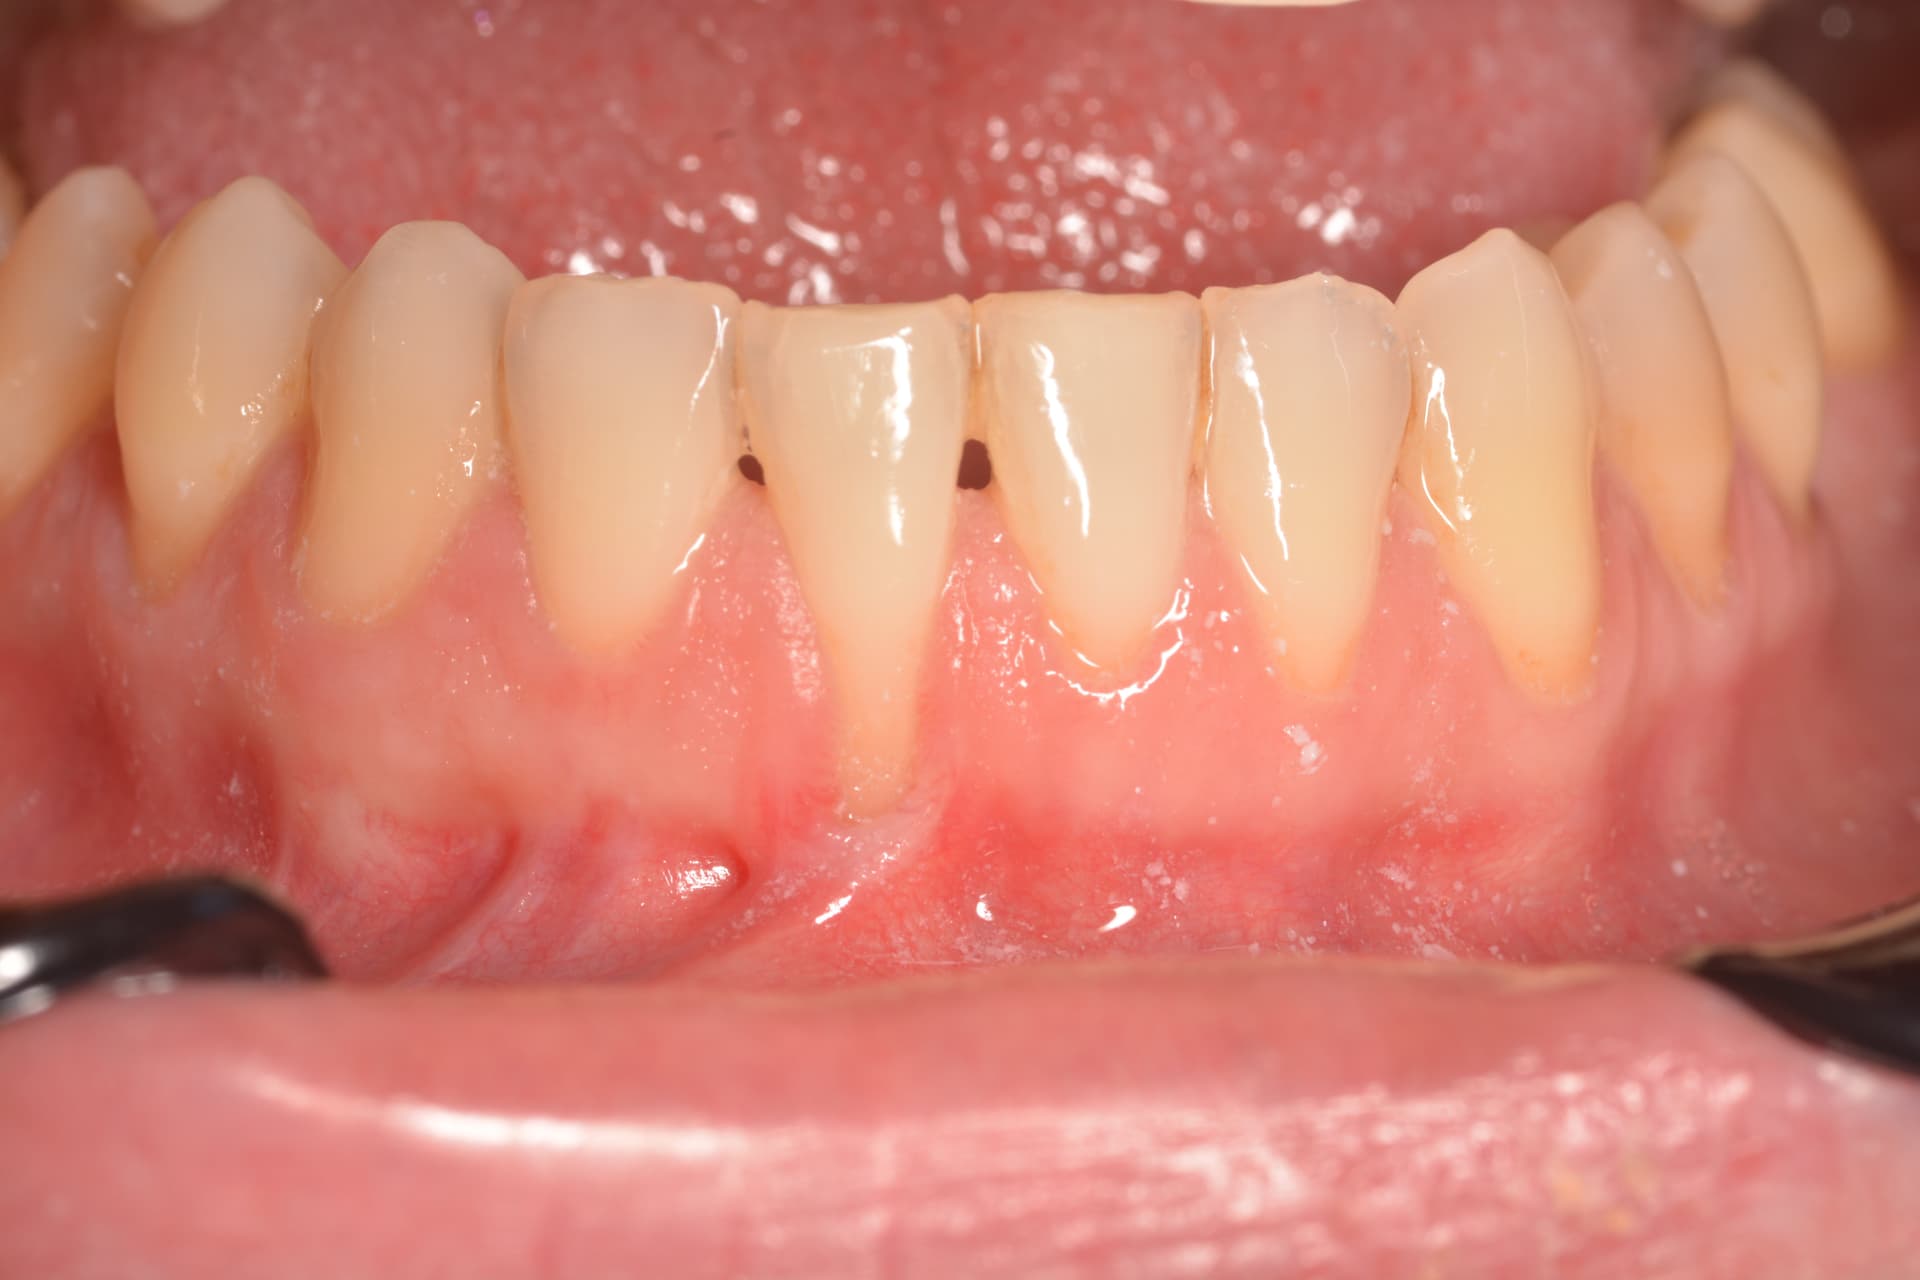

Tratamiento de recesión radicular en incisivo inferior mediante injerto de tejido conectivo